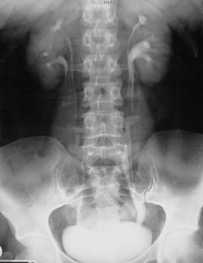

КТ, корональная реформация. Агенезия правой почки.

Торакальная дистопия диагностируется при проведении профилактической флюорографии или обзорной рентгенографии грудной клетки. Дистопированная почка чаще определяется как плотная округлая тень в заднем средостении над диафрагмой. Для правильной диагностики патологии и определения формы заболевания применяются визуализирующие урологические методы – УЗИ почек, ретроградная и экскреторная урография, радиоизотопная ренография (сцинтиграфия), почечная ангиография, МРТ, МСКТ почек.

УЗИ почек позволяет определить отсутствие почки на своем анатомическом месте и дифференцировать дистопию с нефроптозом. Экскреторная урография, как правило, точно выявляет аномальную локализацию почки, степень ее ротации и ограниченную подвижность. При резком снижении функции почек выполняется ретроградная пиелография. В ходе почечной ангиографии устанавливается уровень отхождения почечных артерий от ствола аорты. Дифференциальную диагностику аномалии проводят с нефроптозом, опухолями почки, кишечника, придатков.